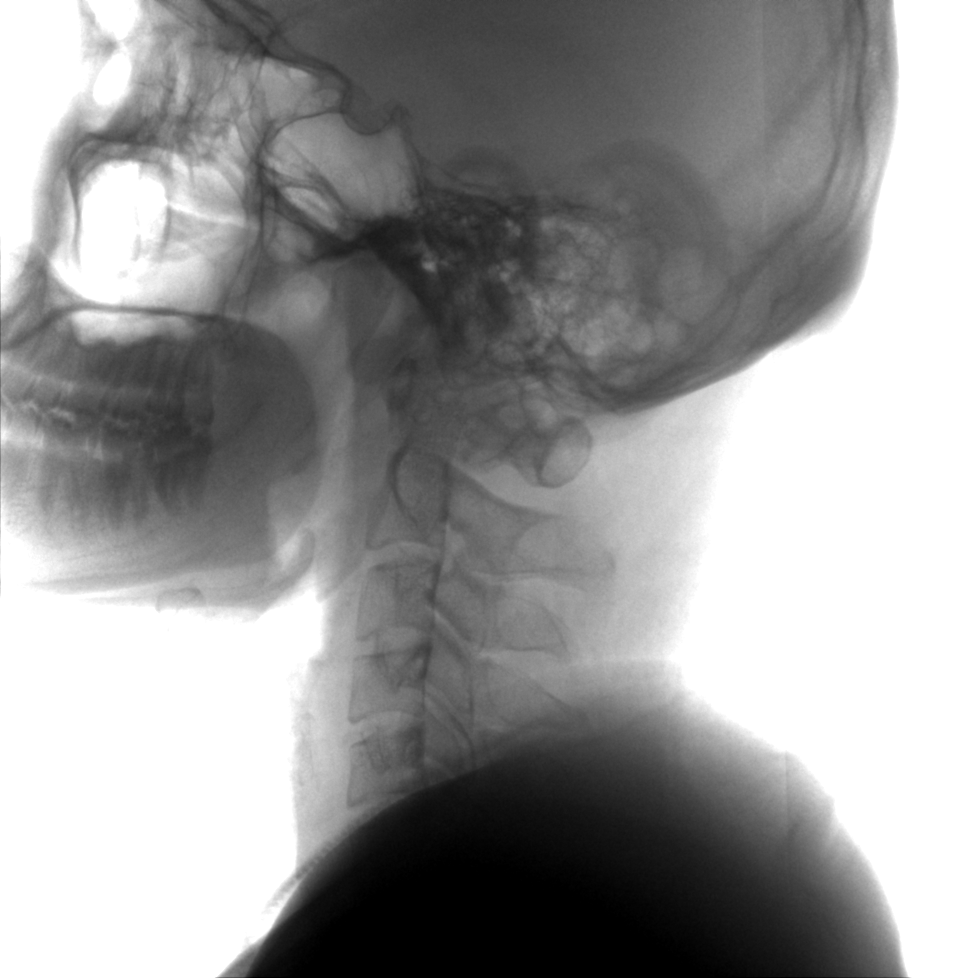

提供更大的術(shù)中三維成像視野,采集更多圖像信息,可一次拍全全段頸椎、全段腰椎、七節(jié)胸椎、雙側(cè)骶髂關(guān)節(jié)、股骨頭及單側(cè)盆骨。